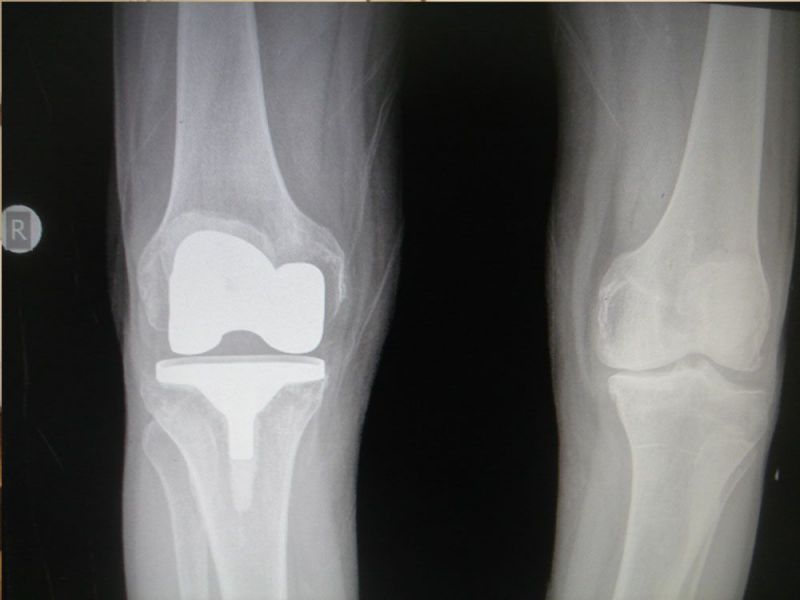

Treatment in the early stages is conservative and may include analgesics, anti-inflammatory, intra-articular injections, physiotherapy. In the final stage, surgical treatment such as total arthroplasty is the method of choice.